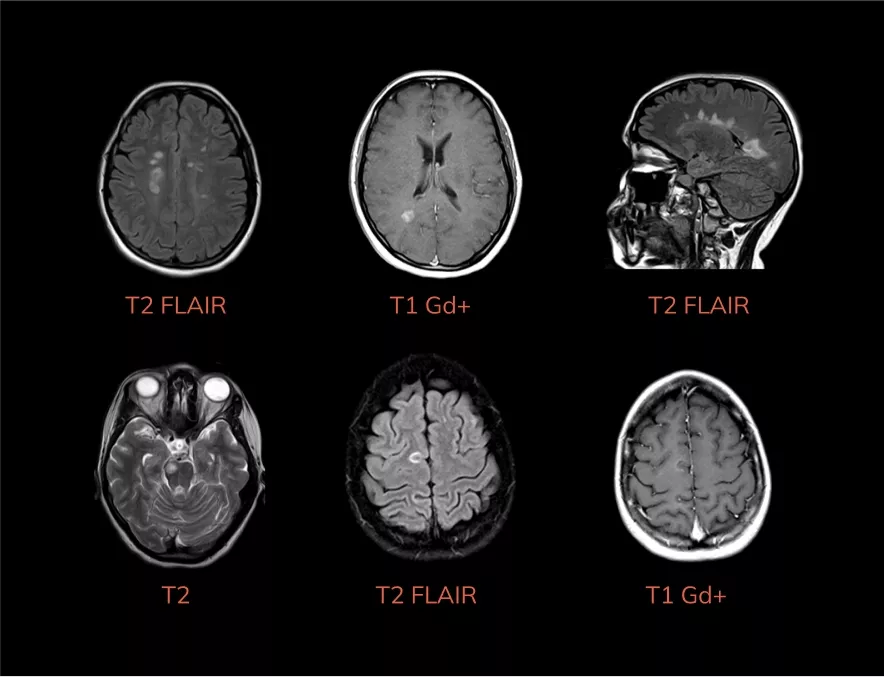

Типичные признаки РС на МРТ

Определяются множественные классические очаги демиелинизации в обоих полушариях большого мозга, мозолистом теле (симптом «пальцев Доусона»), юкстакортикально, в стволе мозга, часть из которых (стрелки) накапливают контрастное вещество.

Определяется классический очаг демиелинизации в шейном отделе спинного мозга, накапливающий контрастное вещество (стрелка).